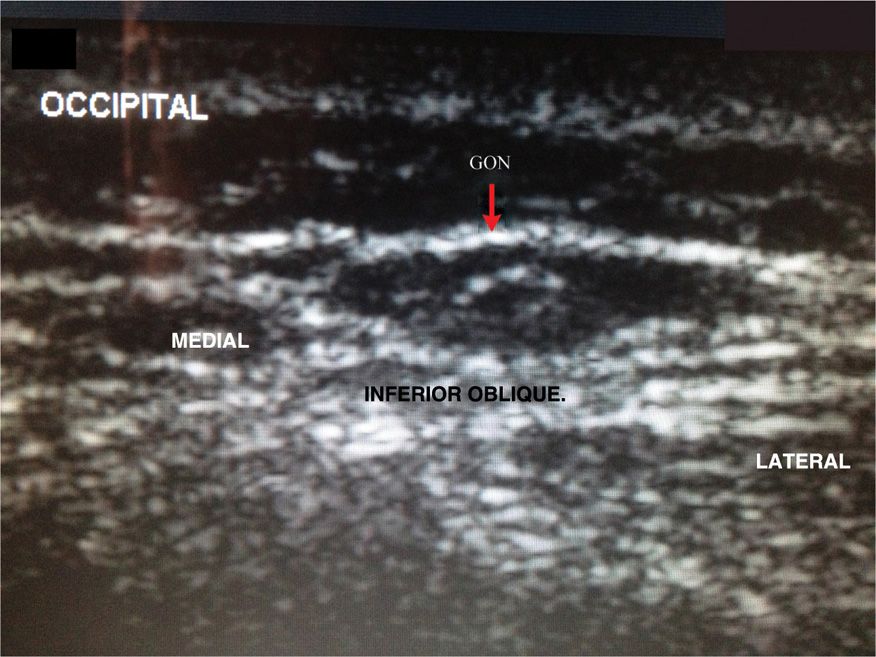

Ultrasound Guided Occipital Nerve Block Cpt Code Occipital Nerve Block The lesser occipital nerve originates from the lateral branch of ventral portion of the c2 and sometimes the c3 spinal nerve. Local injections or nerve blocks, epidural steroid injections, radiofrequency ablation of the planum nuchae, electrical stimulation, rhizotomy, ganglionectomy, nerve root. Review alternative techniques for performing an occipital nerve. The provider injects an anesthetic and/or steroid agent into the greater. Cpt Code Occipital Nerve Block.